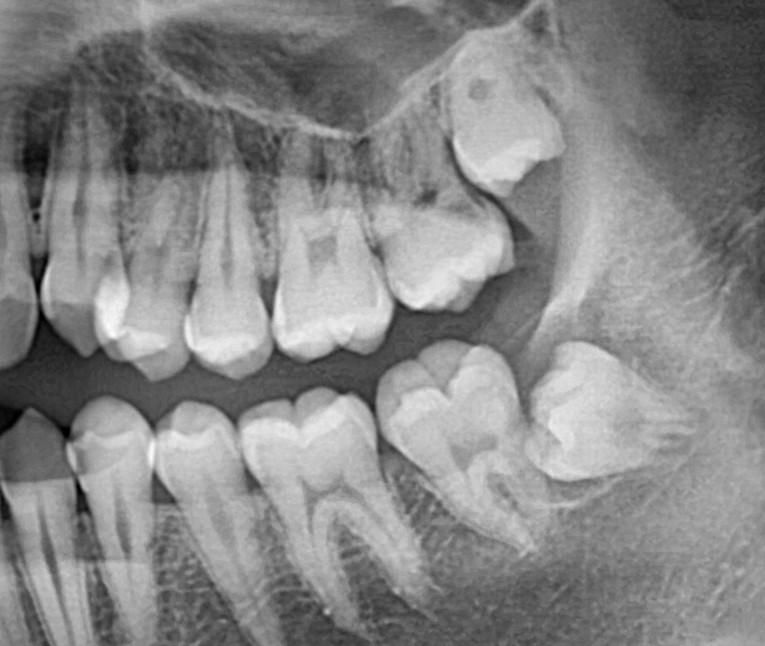

이거 인접면 충치 맞나요? 한 번만 도와주십시오ㅠㅠ

사랑니 발치하러 치과에 갔는데 26번 27번 치아 사이에 인접면 충치가 있다고 하네요,,, 아프거나 시린 적은 한 번도 없었는데 인레이 치료를 해야 한다고 합니다. 과잉진료가 아니라 진짜 충치 맞나요?ㅠㅠ

파노라마 사진상으로는 치아 사이에 충치가 잇는거 같습니다. 정확한건 작은 사진을 찍고 검진을 다시 해보셔야될것같습니다.

위 사진만 보고 인접면 충치여부를 정확히 판단하기는 어렵습니다 치아가 겹쳐보이지 않는 치근단 사진이 필요합니다

26,27 사이는 아주 깊은 충치가 있어보이진 않습니다

오히려 사랑니와 어금니 사이 충치는 있어보입니다